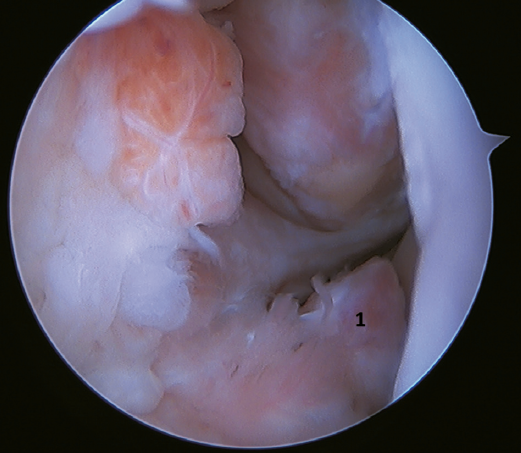

Otro punto de interés es la presencia de os subfibularis; en estos casos, existe la opción de la fijación, si bien no suele ser factible y la mejor opción terapéutica es su exéresis y reconstrucción, debido a la imposibilidad de realizar una reparación directa(60) (Figura 4).

Un reciente consenso(64) recomienda la reconstrucción del LTFA y el LCF (Figuras 5 y 6) en aquellos casos de laxitud generalizada o cuando existe una mala calidad tisular. Otras indicaciones serían cuando existen dudas de la estabilidad subtalar o en aquellos pacientes con rotura del LCF. Para algunos autores, el IMC superior a 30 kg/m2 también sería una indicación para esta técnica.

Figura 5. Rotura del ligamento talofibular anterior y del ligamento calcaneofibular con mala calidad tisular del remanente ligamentoso.